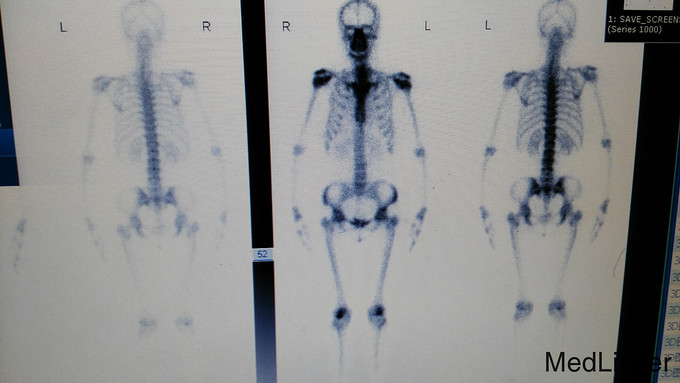

骨痛,退行性骨软骨病1例

女,51岁。以“骨痛5年,加重半年”为主诉入院。 患者于5年前无明显诱因出现双膝关节痛,表现为用力后疼痛,于骨科医院行膝关节MR示“半月板损伤”,余记录不详。患者自觉症状逐渐加重,并出现其他部位疼痛,如髋部、肘部、肩部等,遂先后多次于外院就诊,均未查明原因。3天前,患者再次于骨科医院就诊,据前MR诊断为“骨梗死”,现为求进一步诊治入我院。

诊断:骨痛,退行性骨软骨病 治疗:止痛及予葡立胶囊口服。定期复查膝关节MR及骨平片。